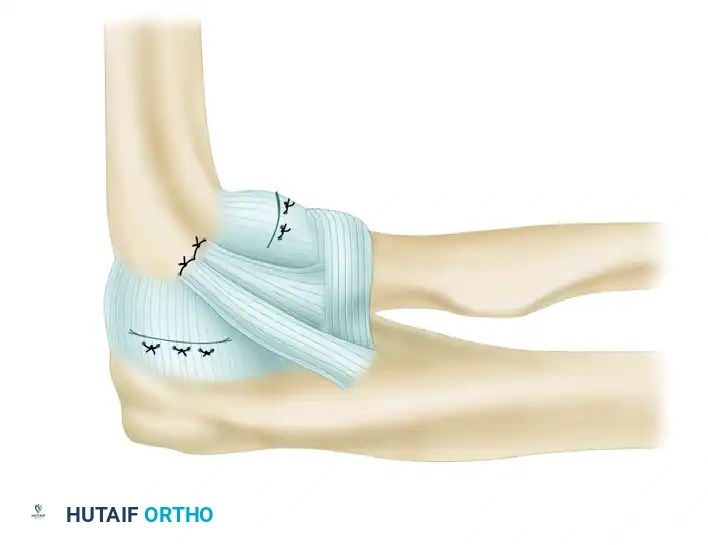

3. Ligament Imbrication and Advancement

Before graft placement, the native, attenuated tissues are managed. Perform an imbrication and advancement of the ulnar band of the radial collateral ligament and the radial part of the radial collateral ligament. This is accomplished using a Bunnell suture technique, placing the sutures through drill holes at the anatomical origin of the ligament in the humerus. This plicates the posterior and anterior capsule, providing a robust secondary restraint.

- The common extensor origin is securely reattached to the lateral epicondyle using transosseous sutures or suture anchors.